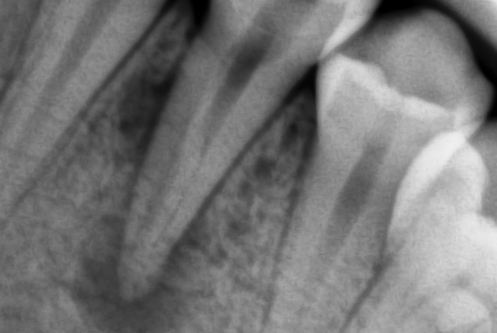

В стоматологической клинике "5 Принципов" в Симферополе мы гордимся тем, что каждый пациент получает индивидуальный подход и безупречный результат в области эндодонтического лечения под микроскопом. Наши специалисты применяют современные цифровые технологии, микропроцессорные и нейромодуляционные инструменты, что позволяет достичь максимальной точности и минимального дискомфорта. В портфолио клиники — широкий спектр кейсов: от первичной диагностики пульпита до сложной ретенированной резорбции и повторной эндодонтии. Мы беремся за зубы любых степеней сложности: от моляра до резцов, используя щадящие концевые инструменты и безболезненные методы постоянной анестезии. Все процедуры проходят под увеличением, что обеспечивает точное удаление инфицированной ткани и сохранение естественной анатомии зуба.Особое внимание мы уделяем постпроцедурному наблюдению: контроль за герметичностью заполнения корневых каналов, профилактические рекомендации и возможная корректировка плана лечения при необходимости. В "5 Принципах" мы разумно сочетаем комфорт, эстетическую привлекательность и долгосрочную функциональность. Результат — здоровые зубы, уверенная улыбка и спокойствие наших пациентов в Симферополе. Запишитесь на консультацию и убедитесь сами в нашем подходе к качественному эндодонтическому лечению.